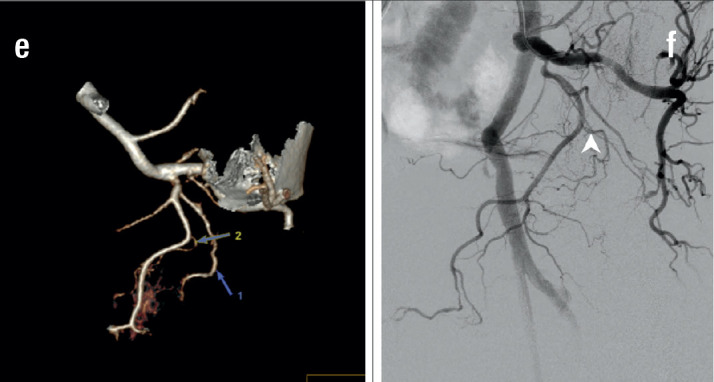

Objective: The study aimed to describe the anatomy and imaging findings of the prostatic artery (PAs) on 3D rendering dual-energy multi-sequence computed tomography (DECT) in patients with symptomatic benign prostatic hypertrophy (BPH) treated by prostatic artery embolisation (PAE).

Methods: The study was conducted on 64 patients with BPH who underwent DECT scans with 3D rendering of the pelvic artery before intervention from August 2022 to November 2023. The PAs were independently evaluated for each side, focusing on the number of branches, origin, tortuosity, atherosclerotic plaque, and anastomoses with adjacent arteries.

Results: Among 128 pelvic sides where the PAs can be observed, the rate of finding 01 prostate artery on each side was high (96.1%), and the rate of 02 prostate arteries on each side was rare (3.9%). In 133 prostatic arteries, the most common type of prostatic artery according to origin is type I (29.6%), followed by type III (24.6%). The atherosclerotic prostatic artery rate is 24.6%, and the average diameter is 1.5±0.4 mm. The tortuosity prostate artery accounted for 74.6%. The anastomosis to the contralateral prostatic artery rate is 48.4%, followed by the penis and rectum anastomoses.

Conclusion: PAs have abundant original varies between the left and right sides and between patient to patient. The most common form arises from the internal pudendal artery.